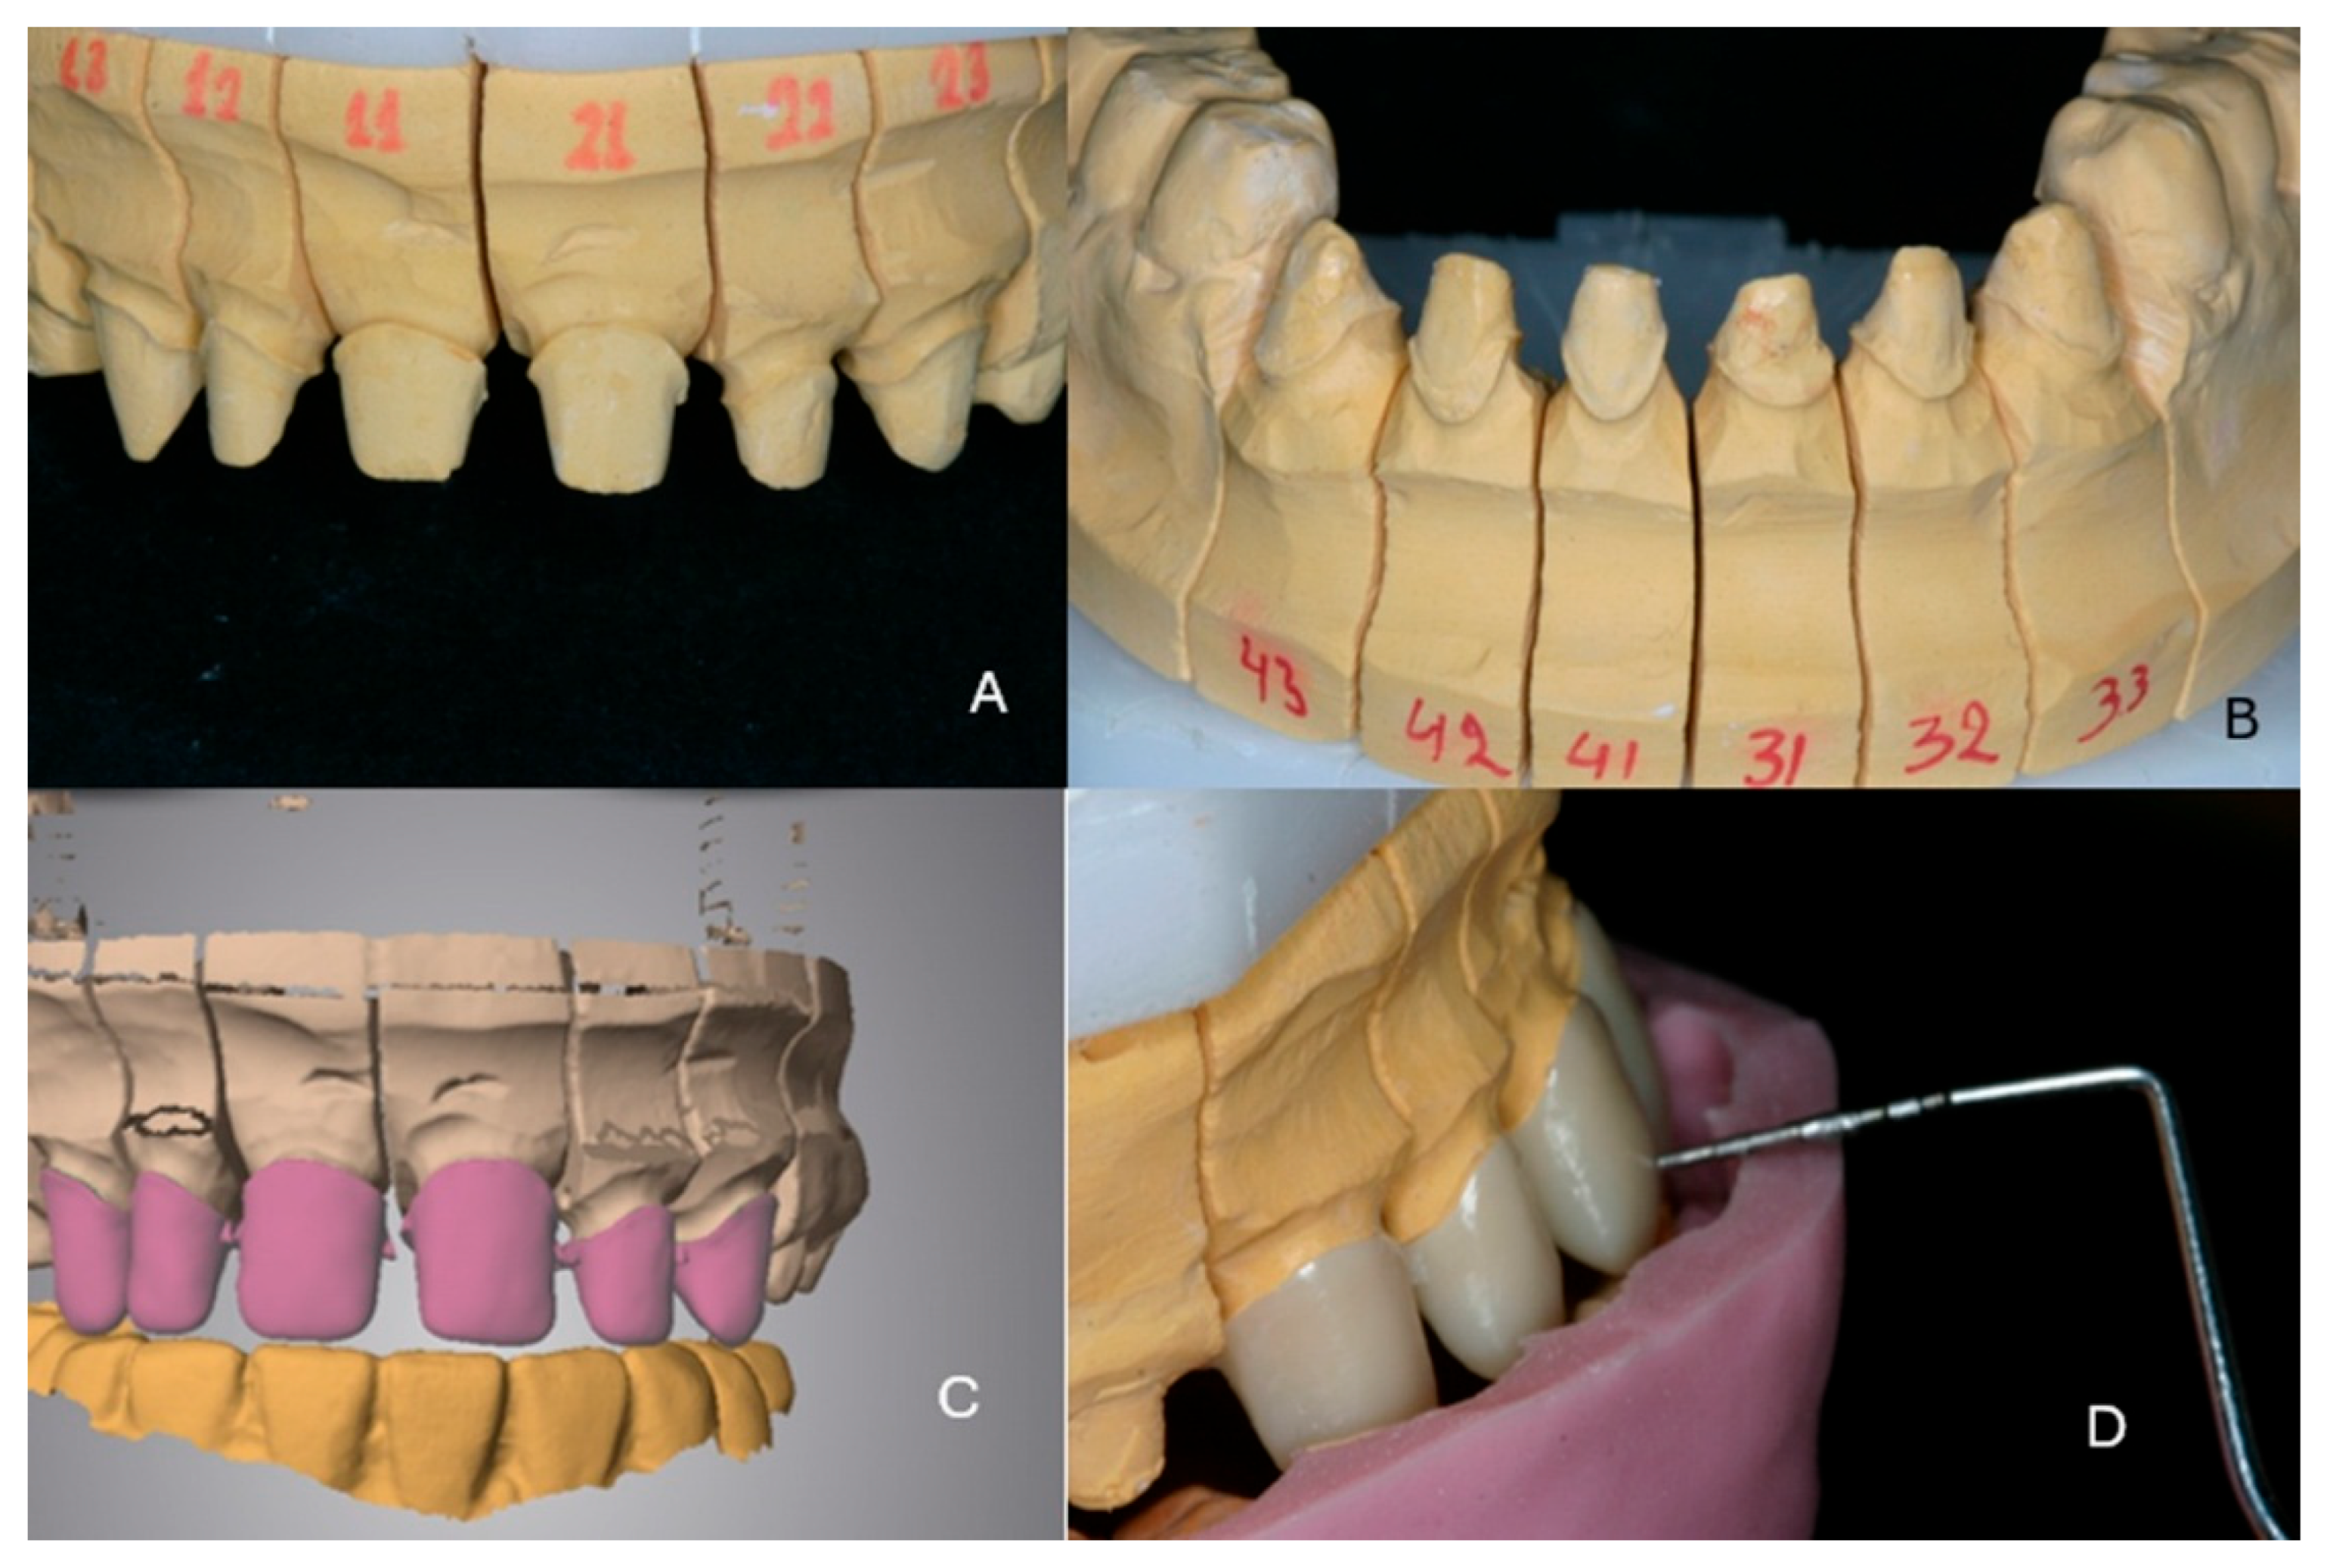

Full Mouth Rehabilitation with All-Ceramic Restorations in a Patient with Amelogenesis Imperfecta: A Case Report with 10-Year Follow-Up

2. Case Presentation